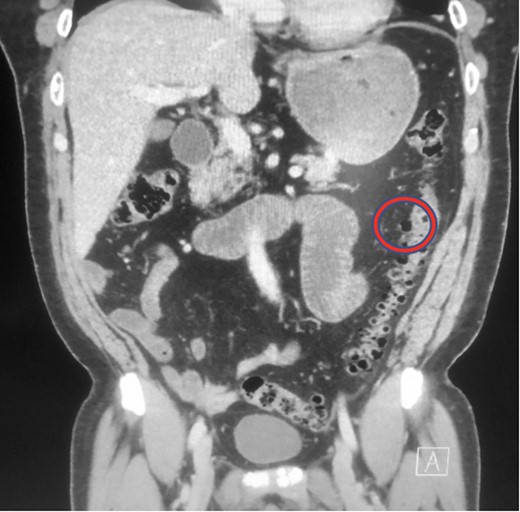

The patient’s WBC count was 15.10 k/μL (3.80–10.80 k/μL) and all other laboratory data was within normal limits. A chest x-ray was unrevealing. An abdominal and pelvis CT with IV contrast revealed a small collection of air and debris adjacent to a loop of mildly thick-walled small bowel in the left lower quadrant measuring roughly 2.3 × 1.9 × 2.0 cm3, with a small adjacent focus of apparent extraluminal air (Fig. 1). The CT also did reveal extensive colonic diverticulosis; however, the radiographic evidence was suggestive of the possible sequelae of an acute perforated small bowel diverticulitis as opposed to a perforated colonic diverticulitis.

Abdominal CT demonstrating collection of air and debris. Area of interest is circled in red.